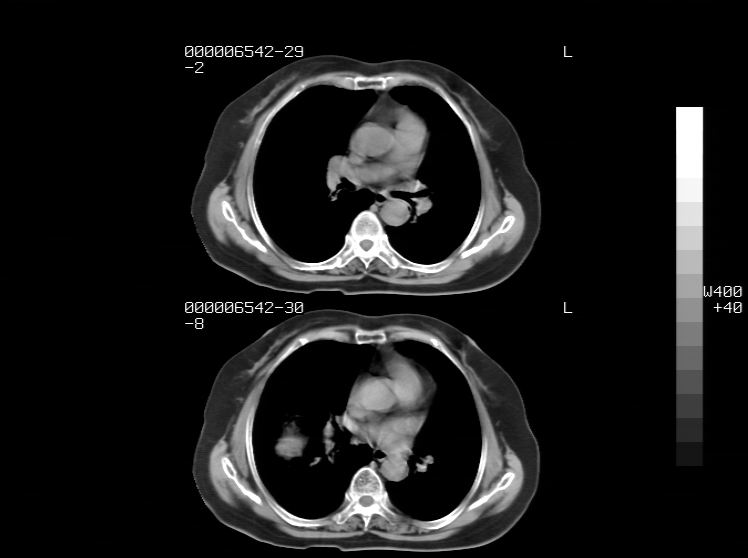

标题: CT24039:请会诊,女70岁,彩超考虑胆囊结石 [打印本页]

标题: CT24039:请会诊,女70岁,彩超考虑胆囊结石

右侧膈膨升,胆囊壁厚,右侧肾脏缺如。病史?

右侧膈膨升,右肾脏切除术后

右侧膈膨升,肝内钙化灶,胆囊壁厚,右侧肾脏缺如。病史?

右膈膨出,肝脏变异,肝内钙化,右肾缺如,脾大。

右侧膈膨升,肝内胆管结石?

右侧肾脏缺如。病史?

右侧膈膨升,胆囊壁厚,右侧肾脏缺如,增强,腔静脉旁是否是移位肾

肝脏变异致膈升高,肝左叶肝内胆管结石.右肾萎缩,左肾代偿肥大.

胆囊ct未见确切异常,请结合b超。右侧肾窝未见确切肾脏影,右肾萎缩?异位?

右侧膈膨升,肝内钙化灶,胆囊壁厚,右肾萎缩或发育不良。